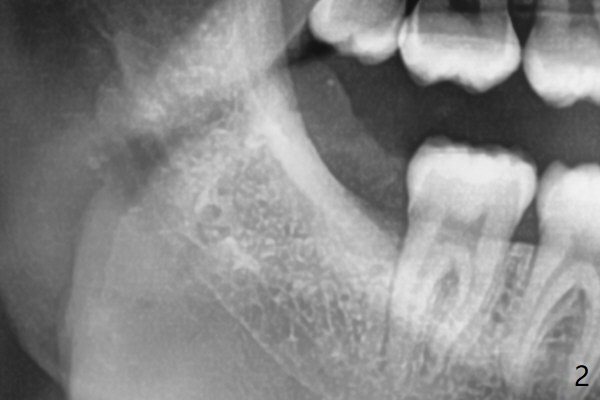

#32 has fused apices, which need sectioning before removal (Fig.1).  A piece of Osteogen plug is inserted to the socket before suturing (Fig.2).